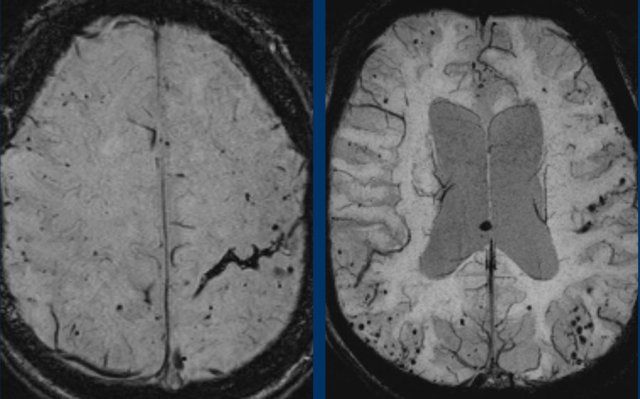

These small hemorrhages are also called microbleeds.

Notice how numerous these small hemorrhages are and primarily located in the perifery of the brain.

This patient presented with a cerebellar hematoma.

Continue with the T1W-image...

The T1W-image shows a hyperintense hemorrhage (arrow).

Hypertensive intracranial haemorrhage together with CAA make up 80% of the causes of intraparenchymal hematomas.

Think of CAA if you see multiple peripheral or lobar haemorrhages in an elderly patient.